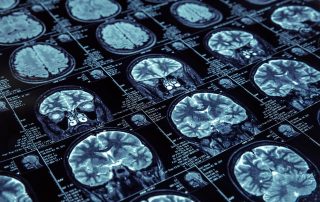

Prise en Charge Pluri-professionnelle des Patients Victimes d’Accident Vasculaire Cérébral (AVC) ischémique aigu

L’accident vasculaire cérébral (AVC) est une maladie grave causée par la rupture (dans 20% des cas) ou l’obstruction (80%) d’un [...]

Traitement chirurgical des conflits vasculo-nerveux : innovations et collaboration

Le traitement des conflits vasculo-nerveux représente un enjeu majeur en neurologie et neurochirurgie. Ces pathologies, souvent invalidantes, nécessitent une prise [...]